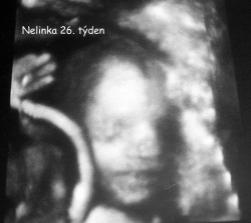

18.září jsme byli na našem 1.IVF... a 8.den od ET se mi "zjevily" nádherné // 🙂... přeju si,aby se všechno vyvíjelo dobře... 29.9 11.den po ET mi pro zhoršení OHSS provedli punkci Douglasova prostoru a odsáli 2 litry žlutého ascitu ☹ Nicméně se mi ulevilo 🙂 HCG ten den 259... 6.10 kontrola HCG - 2950 (18.den od ET)... 10.10 UTZ - čekáme DVOJČÁTKA 🙂 🙂 🙂... 17.10 krvácení a následná hospitalizace, UTZ - dvojčátkům bijí srdíčka, 20.10 HCG - 56000, 25.10 propuštění z nemocnice... 31.10 poslední kontrola v CARu, dvojčátka mají 2 a 2,1 cm... 11.11 UTZ - dvojčátka mají 3 cm... 24.11 UTZ - dvojčátka mají 9 cm (ale moc se mi to měření nezdá, ve čtvrtek na screeningu se ukáže pravda, čeká nás 3D 🙂) 27.11 screening I.trimestru - miminka jsou zdravá, od hlavičky po prdelku mají 7 cm... 19.12 3D - miminko "A" je chlapeček, "béčko" chce zůstat zatím v utajení 🙂 tak snad příště 🙂... 8.1 3D - miminko "B" je holčička 🙂 19.1 echokardiografie - obě srdíčka jsou zdravá 🙂 20.1 screening II.trimestru - vše OK, miminka mají 360 a 364 gramů 🙂 26.1 UTZ - chlapečkovi se ztratil pindík a najednou čekáme 2 holčičky 🙂) Doufám, že už je to definitivní 🙂) 19.2 UTZ 3D4 - holčičky potvrzeny!!! 🙂 mají každá téměř 800 gramů! 🙂 20.3 UTZ - holčičky mají 1700 a 1800 gramů! 8.4 UTZ - holky mají neuvěřitelné váhy 2415 a 2600 gramů! 11.5 nástup do nemocnice... 11.května ve 20,03 se nám akutním císařským řezem narodila Eliška (2970/48) a o minutu později Nelinka (3200/50).Jsme nejšťastnější rodiče na světě! 🙂